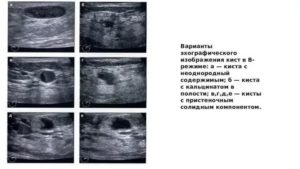

Киста с пристеночным солидным компонентом

Киста имеет размеры от 2 до 8 см. Описано 4 эхографических варианта строения кисты жёлтого тела.1. При 1-м варианте наиболее часто киста имеет сетчатое строение средней эхогенности. В большинстве случаев сетчатый компонент выполняет всю или бульшую часть кисты.

2.

При 2-м варианте содержимое кисты однородное и анэхогенное. В её полости определяются множественные или единичные, нежные, полные или неполные, неправильной формы перегородки.

3. При 3-м варианте в полости кисты определяются плотные, высокой эхогенности включения (сгустки крови).

Чаще они имеют небольшие размеры (1—1,7 см в диаметре), единичны (1—3) и локализуются пристеночно. Эти образования могут иметь как неправильную форму, так и форму булавы или веретена.

4. При 4-м варианте содержимое кисты полностью однородное и анэхогенное. Её эхографическое изображение напоминает фолликулярную кисту.

Несмотря на различия внутреннего строения кист жёлтого тела, их звукопроводимость всегда высока. Толщина стенок колеблется от 2 до 4 мм, составляя в среднем 2,8±0,4 мм.